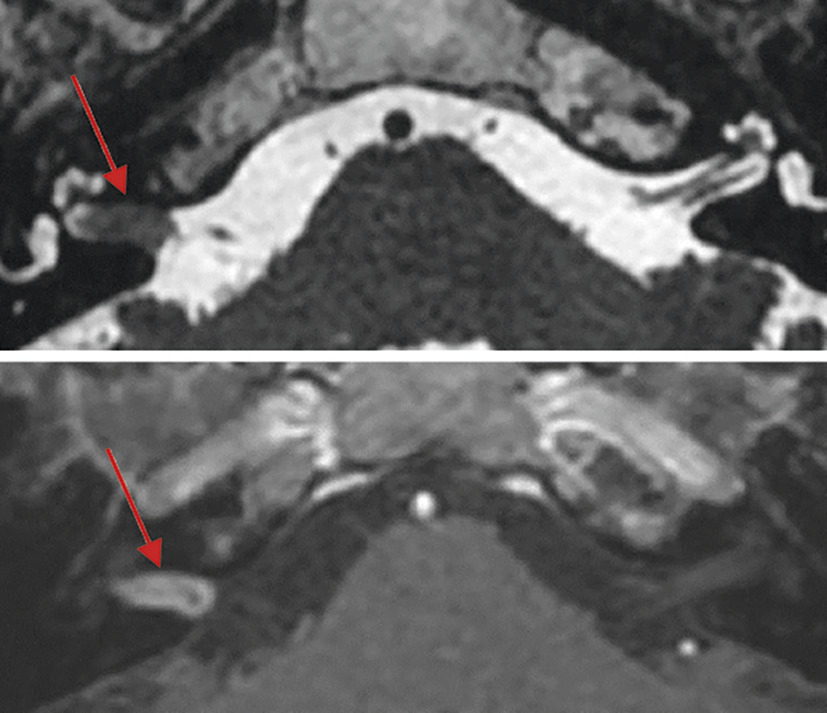

Toute surdité unilatérale ou asymétrique impose une IRM pour détecter un schwannome vestibulaire, tumeur bénigne développée aux dépens du nerf vestibulaire inférieur (fig. 4) ou d’autres processus expansifs de l’angle ponto-cérébelleux.

IRM cérébrale avec étude spécifique des conduits auditifs internes (CAI) et des oreilles internes. Analyse fine des paquets nerveux acoustico-faciaux et des oreilles internes. Séquences sans et avec injection de gadolinium notamment pour mettre en évidence un schwannome (prise de contraste nodulaire centrée sur le nerf vestibulo-cochléaire) ou encore une labyrinthite.